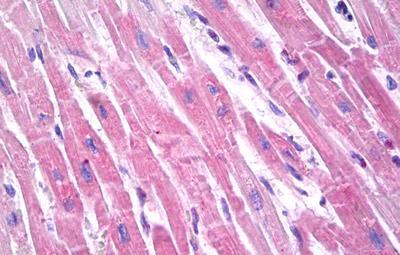

IHC (Immunohistochemistry)

(Anti-Brain Natriuretic Peptide 32 antibody IHC of human heart. Immunohistochemistry of formalin-fixed, paraffin-embedded tissue after heat-induced antigen retrieval. Antibody concentration 10 ug/ml.)